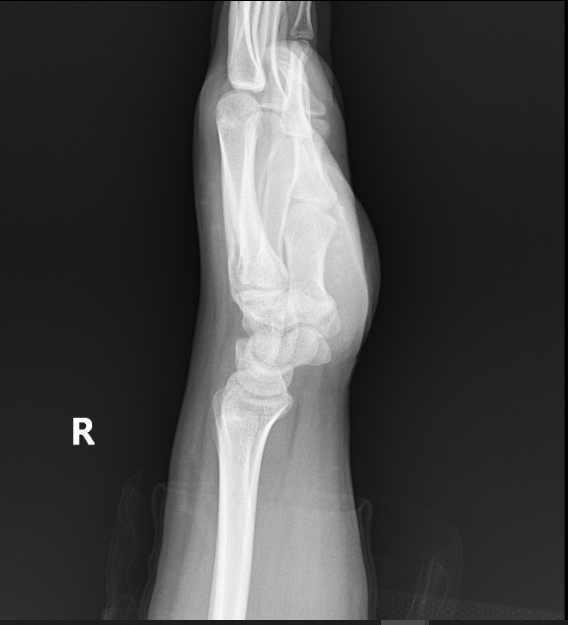

우측 손목 바깥쪽 척골 근처 통증으로 처음엔 힘줄염 진단받고 소염진통제 3개월 먹고 체외충격파 여러번 받았는데도 좋아지지 않아서 mri찍었습니다. mri상 힘줄은 전혀 염증이 없고 tfcc쪽 상태가 아주 깨끗하진 않지만(다 검정색이어야하는데) 아주 나쁘고 그렇지도 않다고 들었어요. 그래서 좀 찾아보니 척골충돌증후군하고 증상이 비슷해서 혹시 사진상 척골충돌증후군에 해당되는지 여쭈어봅니다.

엑스레이상 척골이 과하게 길어서 생기는 충돌증후군은 없습니다.